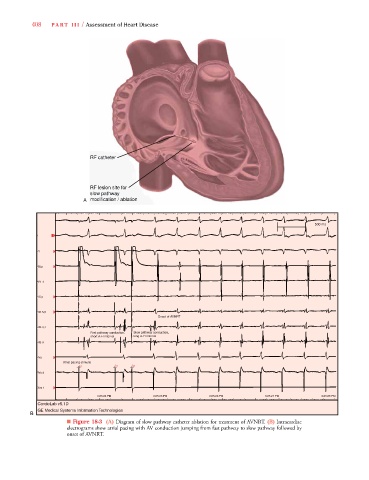

■ Figure 18-3 (A) Diagram of slow pathway catheter ablation for treatment of AVNRT. (B) Intracardiac

electrograms show atrial pacing with AV conduction jumping from fast pathway to slow pathway followed by

onset of AVNRT.